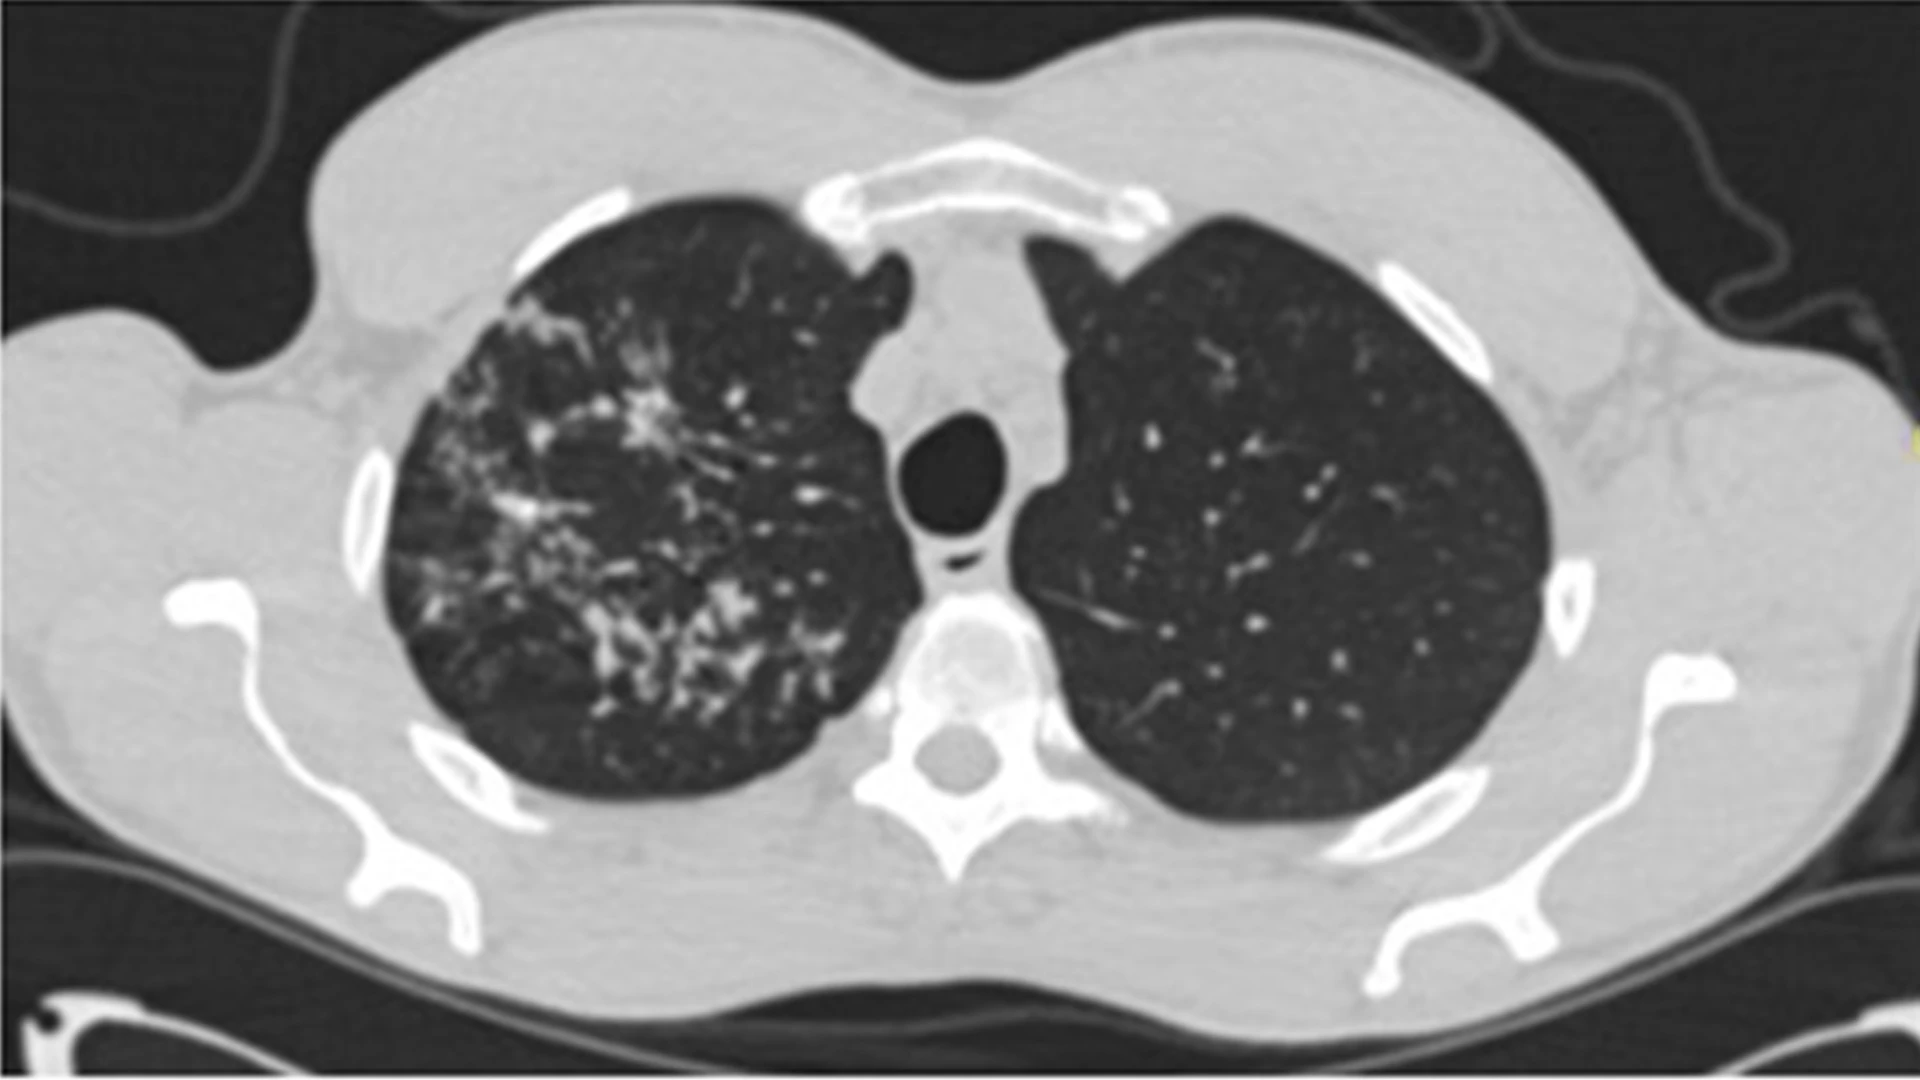

The chest CT also showed a nodular infiltrate in the right upper lobe. A bronchoscopy was performed and obtained positive cultures for tuberculosis.

“In cases like that, we typically recommend a full CT of the chest,” he says. “In this case, the full scan also revealed a host of nodules and infiltrates on the upper right lobe, which indicated tuberculosis. This was a patient who was asymptomatic and thus posed huge public health risks; however, we were able to catch it early and deliver treatment as a result of this program.”